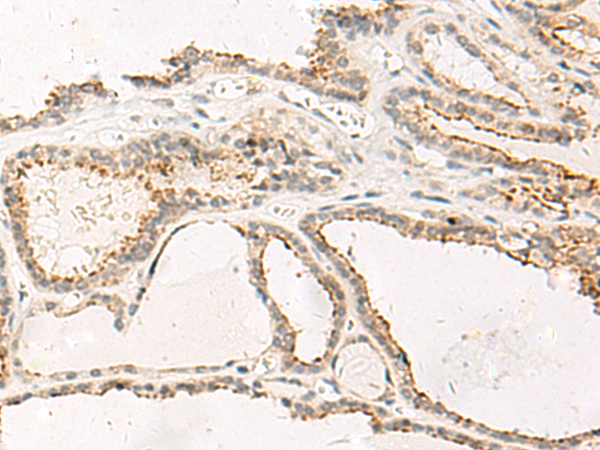

ELISA, IHC

IHC positive control:

Human thyroid cancer

IHC Recommend dilution:

20-100